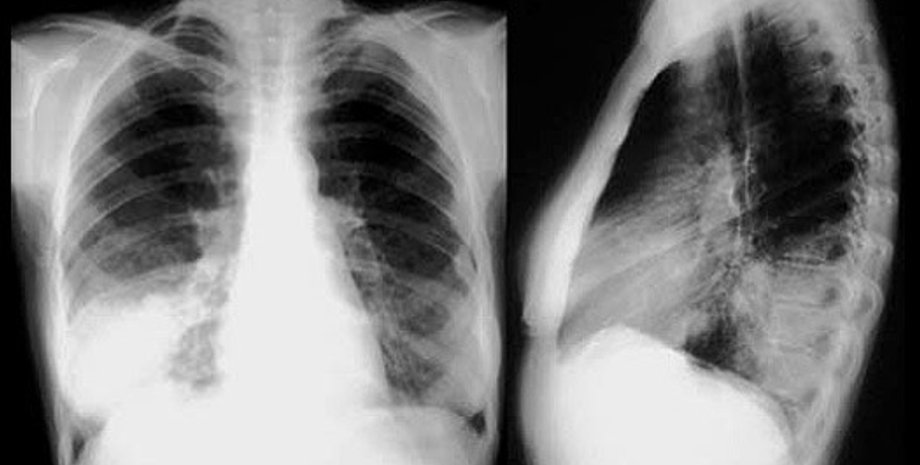

Как сообщает радио ООН, с 1997 по 2007 год в мире каждый год проводилось в среднем 3,5 млрд. рентгенологических исследований. Это на 40% больше, чем в предыдущем десятилетии.

Несмотря на то, что диагностика и лечение с использованием радиации - шаг вперед в развитии медицины, МАГАТЭ и ВОЗ обеспокоены, что зачастую такие процедуры назначаются без достаточных оснований, а используемая доза облучения превышает допустимую. Причина, как правило - недостаточная квалификация медперсонала.